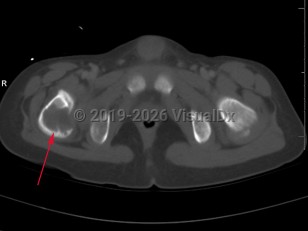

Traumatic hip dislocation